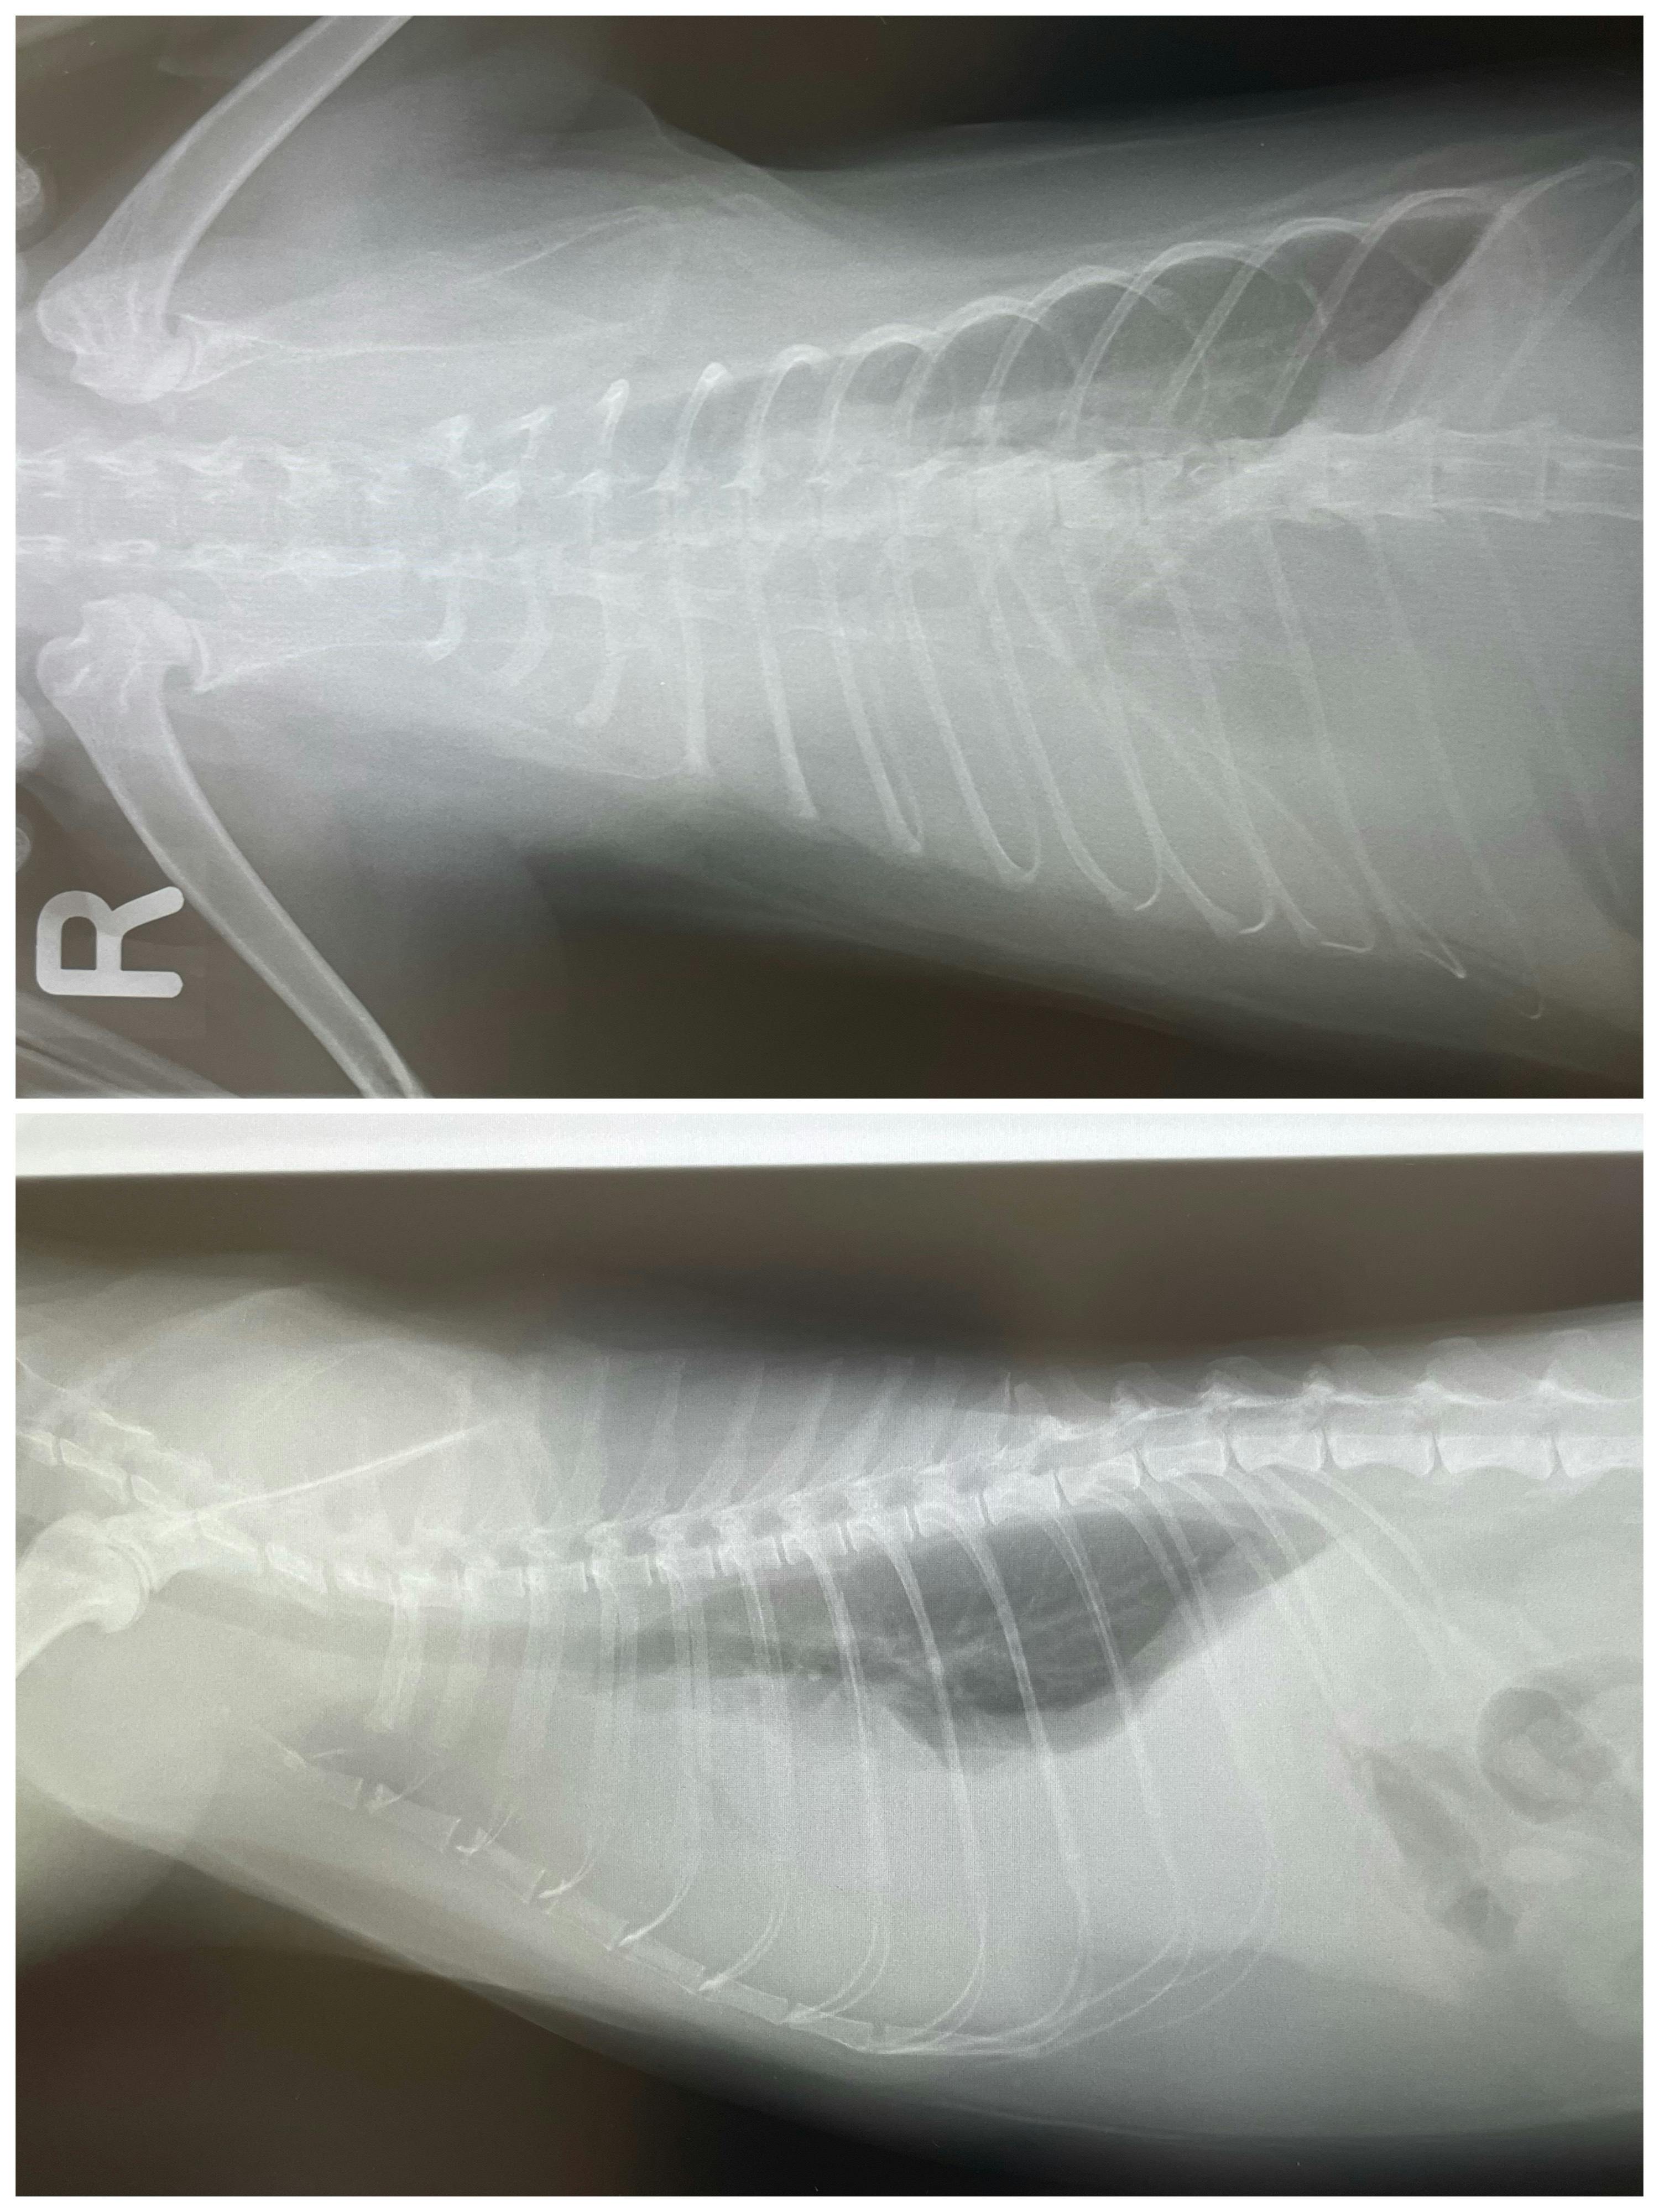

尿路結石で入院した子もきちんと治療し、元気に退院しています。この時の医療費は18万円でした。

肺に膿が溜まり2週間入院した子も居ます。その時は45万円掛かりました。